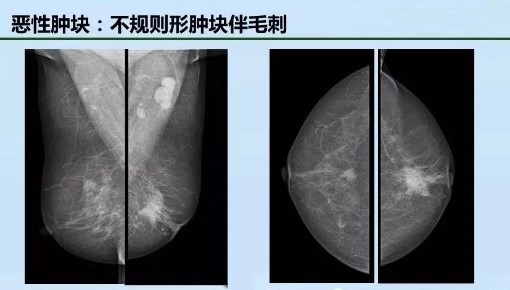

二、发现肿物

在两个不同投照位置均可见到的占位性病变,其中以其边缘征象对判断肿块的性质最为重要,可表现为边缘清晰、模糊、浸润性生长,或可见到从肿块边缘发出的放射状线影。乳腺肿块与其周围乳腺组织相比,多数呈高或等密度,极少数可表现为低密度。